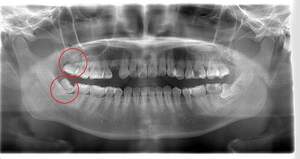

左下の歯茎が腫れている親知らずの症例

- 抜歯前写真(レントゲン、CT等)

左下の親知らず周囲歯肉が腫れていました。

また、手前の歯との間で虫歯もできていました。

| 抜歯内容 | 下顎の親知らずの抜歯希望の患者様です。 智歯周囲炎となっており、初診時では麻酔が効きづらい旨をお話しし、初診時は抗生物質をお出ししました。1週間後、ある程度歯肉の炎症がとれたことを確認して抜歯を行いました。 麻酔を行い、遠心(親知らずの奥側)歯肉と、手前の歯の頬側の歯肉を切開しました。 歯茎を開いて、手前の歯と引っかかっている部分をカットしました。 その後、骨からでている歯冠部(頭の部分)をカットしました。 その後へーベルで歯根(骨に埋まっている部分)を脱臼し、抜歯を終えました。 切開した歯茎を3針縫って、治療終了となりました。 歯茎を切ったため、3日ほど腫れぼったい感じがあったようですが、痛みはほとんどなく、治癒に向かいました。 |